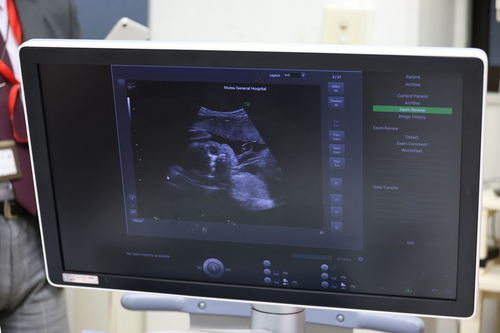

距離の離れた弘前大学医学部附属病院の周産期専門医と、リアルタイムで妊婦さんのエコー(超音波)画像などを共有する「遠隔妊産婦管理システム」が令和7年3月 にスタートしました。

(武田部長)最初の案では共有する情報が「胎児心拍モニタリング」だけでした。陣痛の波と赤ちゃんの心拍を見る機械なのですが、「赤ちゃんが苦しそう」ということはわかっても、「なぜ」苦しいのか、「形の異常」があるかまでは、エコーを使わないと分かりません。

「どうせやるなら、患者さんにも私たちにもメリットが大きい遠隔エコーにしてほしい」と、私からお願いし、弘前大学の先生方もすぐに納得してくださいました

(武田部長)以前は、胎盤の異常などを確認してもらう際、画像データをCD-ROMで郵送していました。それでは結果が出るまでに数日かかってしまいます。

今はエコーなどの画像を送信すれば、リアルタイムでアドバイスをもらえるようになりました。専門医の目がその場で入ることで診療のクオリティが上がりましたし、何より弘前大学医学部附属病院との「相談の距離」がぐっと縮まったと感じています。